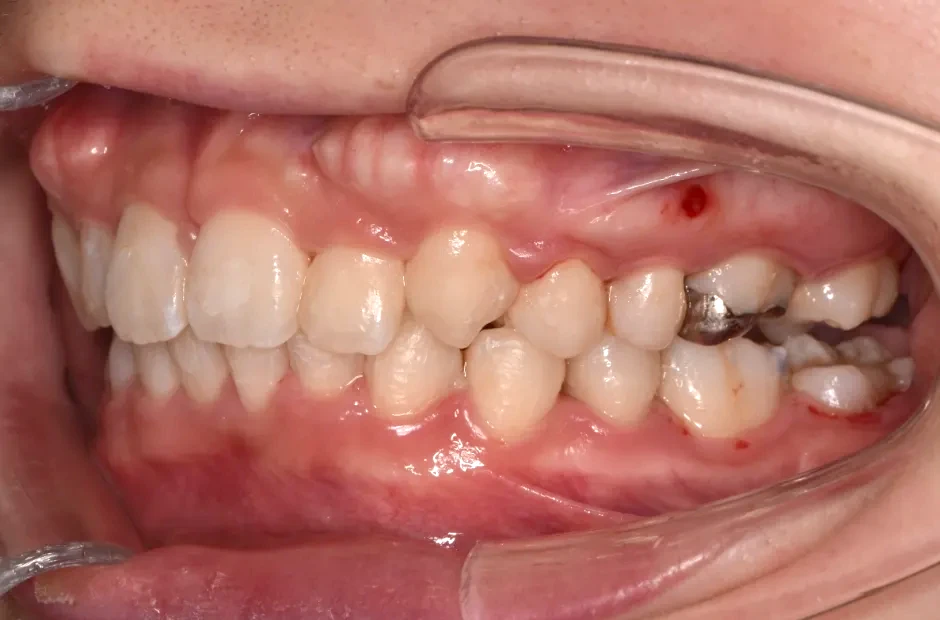

治療前